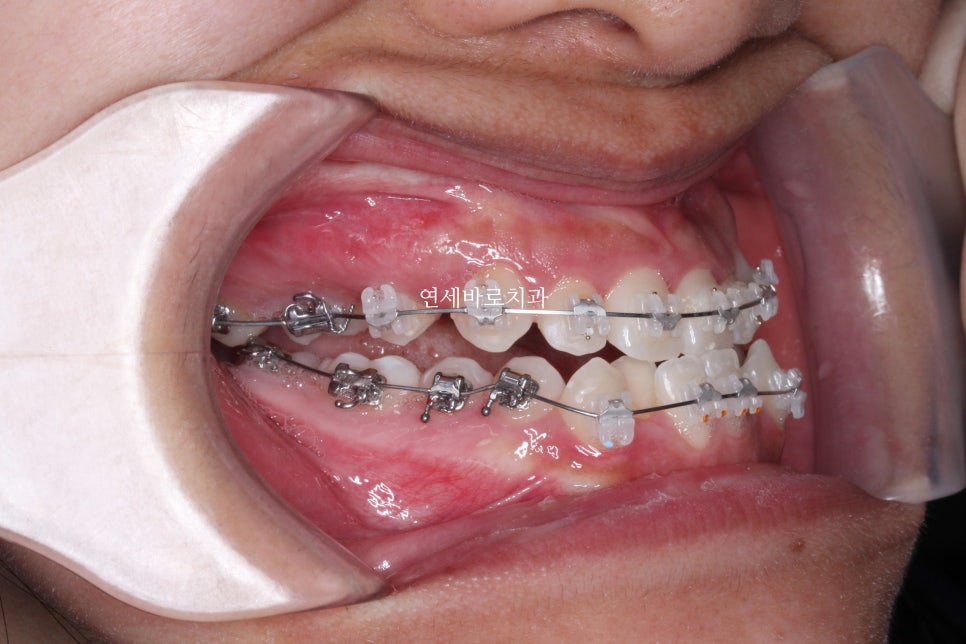

이 환자분은 선수술 까진 아니지만,

수술 전 교정치료가 완료 되기 전에 수술을 했습니다.

학교 입학 등 큰 일정을 맞춰야 했기 때문이죠.

협진을 하는 외과원장님들과 긴말하게 연락하며 치료 교합을 확정했고 문제없이 수술이 완료되었습니다.

중간에 수술도 하시고, 수술 후에 교정치료를 더 진행하셨습니다.